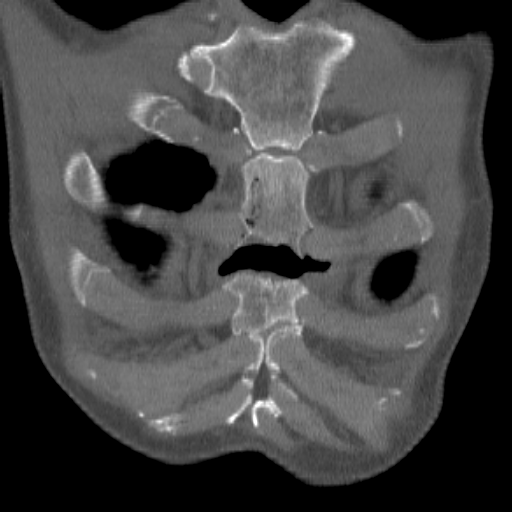

Повреждение грудины, КТ.

После автомобильной травмы с повреждением грудины через пару недель усиливаются боли, температура...